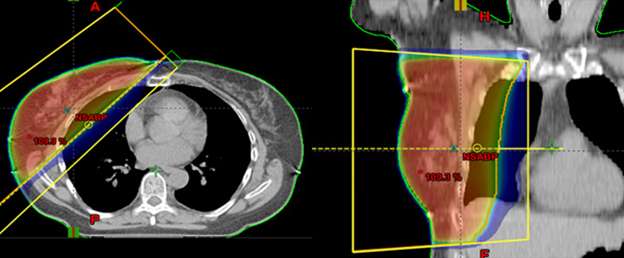

Radiation Biology for Medical Physicists - 1st Edition, Special Techniques of Adjuvant Breast Carcinoma Radiotherapy,

Special Techniques of Adjuvant Breast Carcinoma Radiotherapy, Breast Cancer - Radixact,

Breast Cancer - Radixact, Breast Cancer – Brachytherapy - Radiation Oncology | UCLA,

Breast Cancer – Brachytherapy - Radiation Oncology | UCLA,